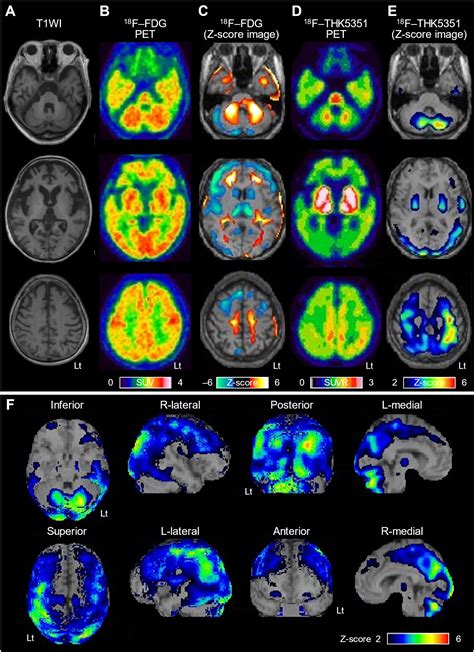

• Imaging Studies: Magnetic Resonance Imaging (MRI) and other imaging techniques can reveal characteristic changes in the brain, such as atrophy and the presence of amyloid plaques.